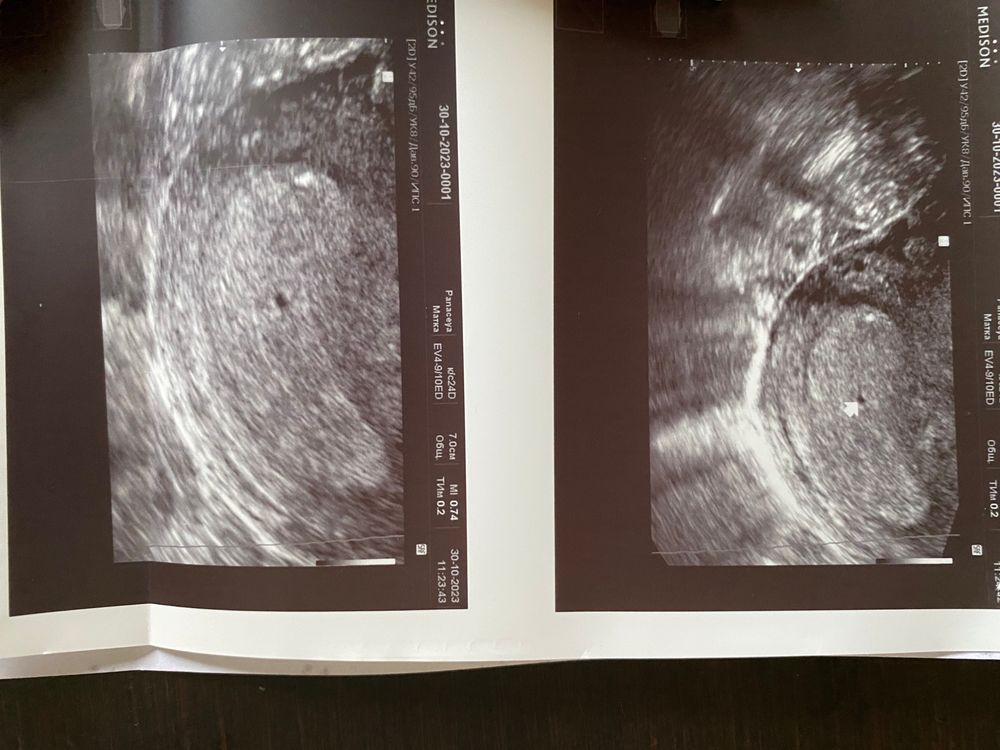

УЗИ, очень переживаю

Девочки всем привет, ничего не понимаю, подскажите пожалуйста, ходила вчера на узи, ктр 2мм, ставят срок 4-5 недель, хотя последние м были 22.09.23, то есть срок то уже больше, сердечко не услышали еще, 1 числа снова на узи, очень переживаю

1 ноября делали узи, ставили срок 4 недели, потом была кровь, побежала опять на узи 6 ноября, стави